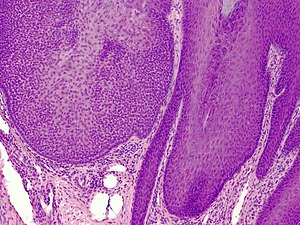

Trichilemmoma. H&E stain. | |

| LM | superficial dermal lesion contiguous with the epidermis; core of lesion has cuboidal cells with round nuclei, eosinophilic-clear cytoplasm; periphery of lesion surrounded by hyaline band, has peripheral palisading |

| LM DDx | trichilemmal carcinoma, basal cell carcinoma, inverted follicular keratosis |

- Superficial dermal lesion contiguous with the epidermis:

- Core of lesion:

- Cuboidal cells with round nuclei, eosinophilic-clear cytoplasm.

- Periphery of lesion:

- Surrounded by hyaline band.

- Peripheral palisading.